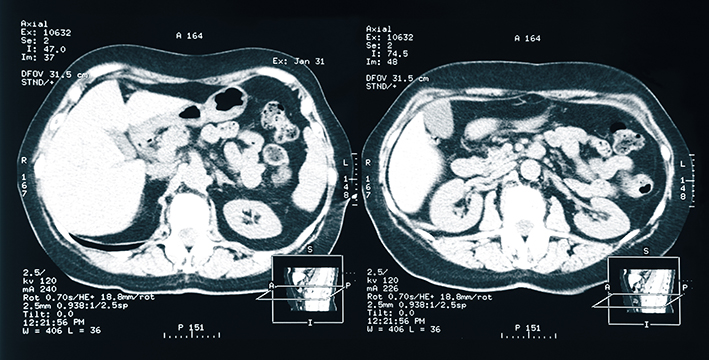

Die akute Nierenschädigung ist eine häufige Komplikation bei Patient:innen auf Intensivstationen und ist mit einem hohen Risiko für Tod, Folgekomplikationen und Ressourcenverbrauch verbunden. Viele dieser Patient:innen erhalten eine Nierenersatztherapie. Diese wird zur Behandlung schwerwiegender Stoffwechselstörungen (z.B. Azidose, Hyperkaliämie, Urämie) und Störungen im Flüssigkeitshaushalt benötigt (Überwässerung). Nach wie vor ist es jedoch unklar, wann genau mit einer Nierenersatztherapie begonnen werden soll.

In dieser großen multinationalen, randomisierten Studie, die bei insgesamt 3019 kritisch kranken Patient:innen mit schwerer akuter Nierenschädigung durchgeführt wurde, reduzierte eine beschleunigte Strategie zur Einleitung einer Nierenersatztherapie die 90-Tage-Mortalität im Vergleich zu einer Standardstrategie nicht. Jedoch zeigte sich bei Patient:innen im beschleunigten Arm eine deutlich höhere Rate an Dialysepflichtigkeit am Tag 90. Dies könnte mit der größeren Häufigkeit von Blutdruckabfällen verbunden sein, die im beschleunigten Arm der Studie signifikant häufiger auftraten. „Unsere Studie klärt ein langjähriges klinisches Dilemma hinsichtlich des Beginns der Nierenersatztherapie bei Patient:innen mit akuter Nierenschädigung ohne akute Krankheitskomplikationen, die einen sofortigen Beginn der Nierenersatztherapie erfordern würden“, meint Michael Joannidis.